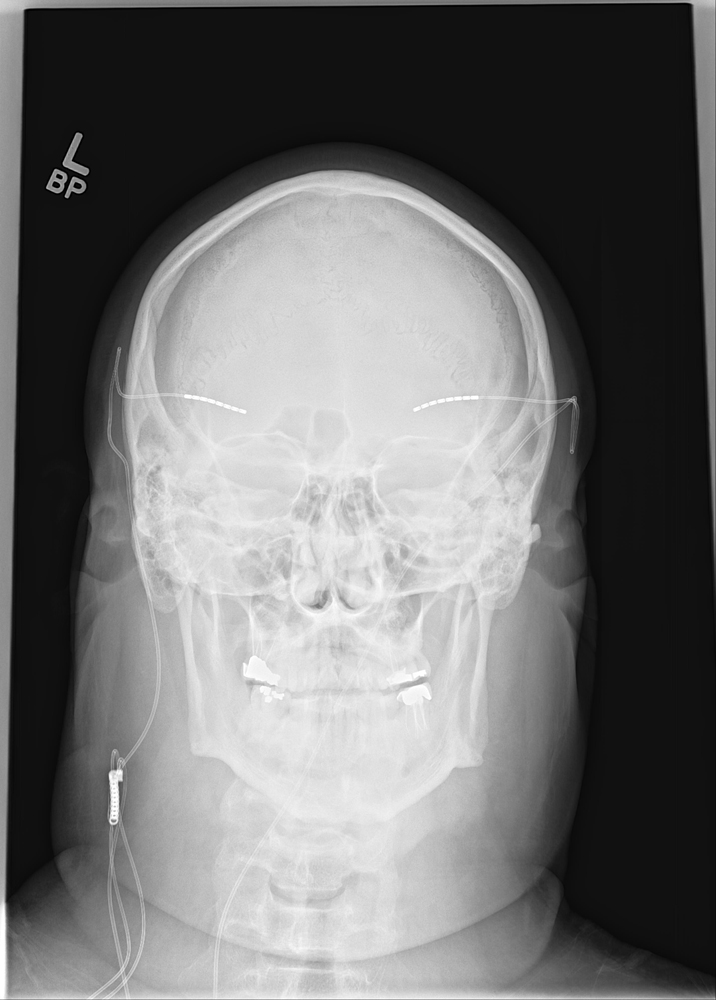

- X-ray — spinal dislocation or slippage, scoliosis, as well as overall spine balance can be assessed via X-rays — as can bone spurs and erosion.